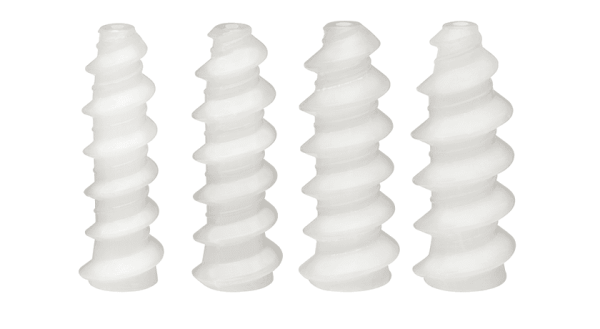

The bio-integrative, metal-free fixation implant delivers metal-like fixation strength while ultimately integrating into the patient’s native bone.